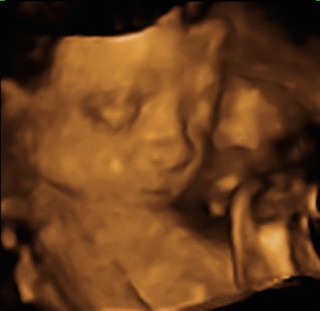

初めての3Dエコー。とても感動しました。寝ていたようであまり動きませんでしたが、お顔は見せてくれました。パパによく似た女の子です。